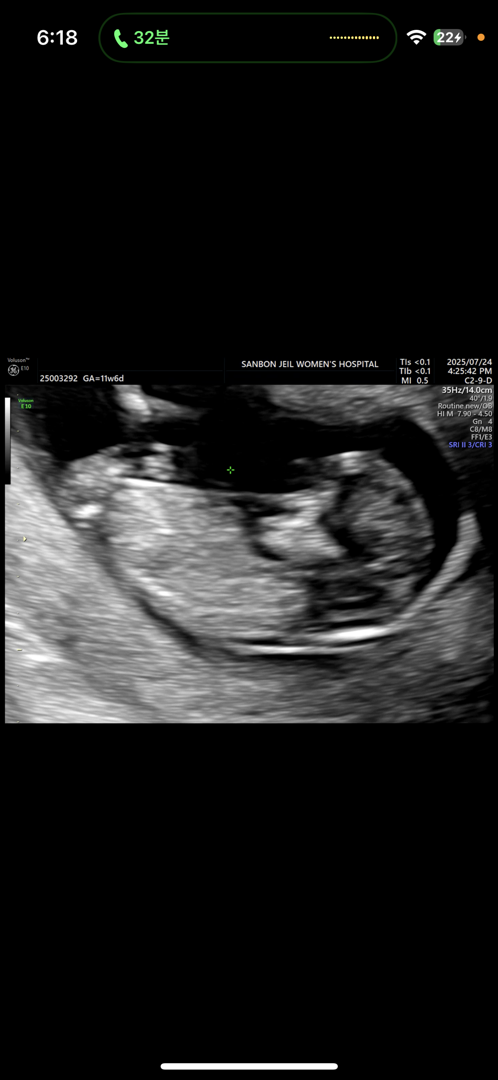

전 성별 너무 궁금해서 그냥 니프티 했어요 ㅋㅋ

딸일까요 아들일까요 …. 제발 ㅠㅠㅠ 너무 궁금해서 미치겠어요

아들일까요 딸일까요 ㅠㅠㅠㅠㅠㅠㅠㅠ 저는 딸 원츄 ….제발 ….

생식기가 좀더 잘 보여야할거 같은데ㅠㅠ 아들같아요..!

감사합니다 아들이였어요🩷